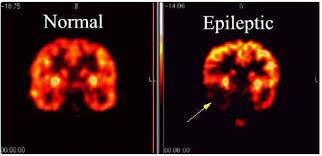

Utilizzando un modello di epilessia nei topi geneticamente modificati, i ricercatori hanno scoperto che le cellule staminali neurali dell’ippocampo smettono di generare nuovi neuroni e vengono trasformati in astrociti reattivi, un tipo di cellula che promuove l’infiammazione e altera la comunicazione tra i neuroni.

Questo lavoro di ricerca ha consentito di confermare l’ipotesi di un precedente lavoro di ricerca. Questa ipotesi ha stabilito che anche se l’ ipereccitazione neuronale non arriva al punto di provocare convulsioni, induce la massiccia attivazione delle cellule staminali neurali e il loro conseguente esaurimento prematuro; come risultato, la neurogenesi (generazione di nuovi neuroni) nell’ippocampo viene cronicamente ridotta.

Anche se il lavoro è stato effettuato su animali, questa scoperta ha chiare implicazioni nella pratica clinica e nella ricerca di nuove terapie per l’epilessia, dato che la generazione di nuovi neuroni (neurogenesi) nell’ippocampo è un processo che è influenzato negativamente dalle crisi epilettiche. ” Mantenere la popolazione di cellule staminali neurali e la loro capacità di generare nuovi neuroni negli esseri umani, ci consentirà di prevenire lo sviluppo di alcuni sintomi associati con l’epilessia e molto probabilmente di mitigare il danno causato nell’ippocampo”, ha sottolineato Juan Manuel Encinas.